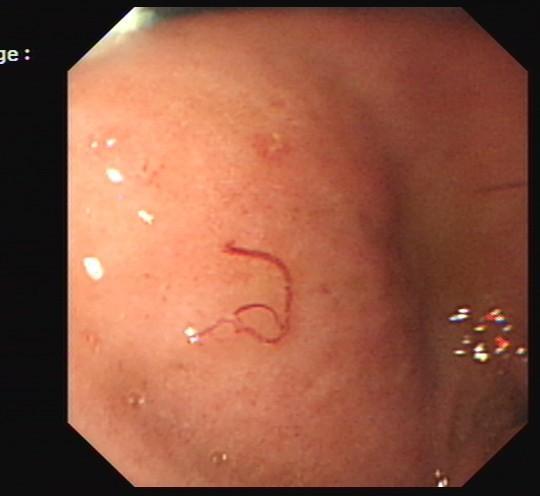

胃内蛔虫

市民胡女士来到襄阳市中医院做胃镜检查,想看看自己胃里是否还有蛔虫

胃蛔虫

人体胃有蛔虫

胃虫图片 真实图片

胃里有虫子